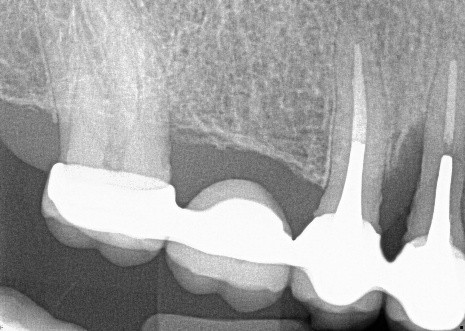

3. (Select ONE OR MORE correct answers)

The radiograph shows evidence of calculus on

4. (Select ONE OR MORE correct answers)